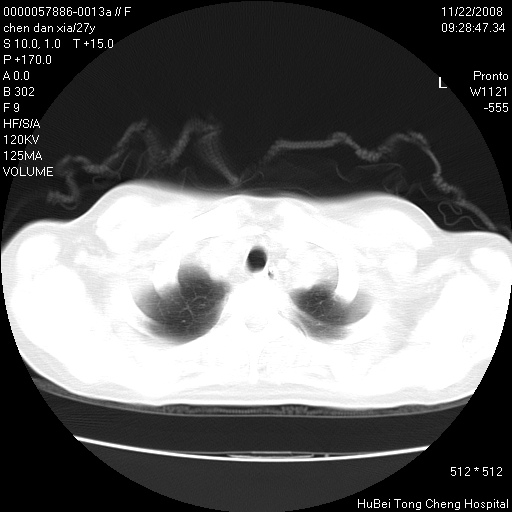

考虑双肺粟粒性肺tb,右侧胸膜增厚.

右下肺见片絮状影,两肺野内分布不均的小结节影,结核并肺内播散可能性大,建议结合实验室检查 .

双肺纹影普多,部分呈网状,支炎或淋巴管炎?

纵隔内淋结肿

局部胸膜增厚

似有粟米状结节。考虑粟粒型肺结核?

好像有微结节,建议薄层以除外结核